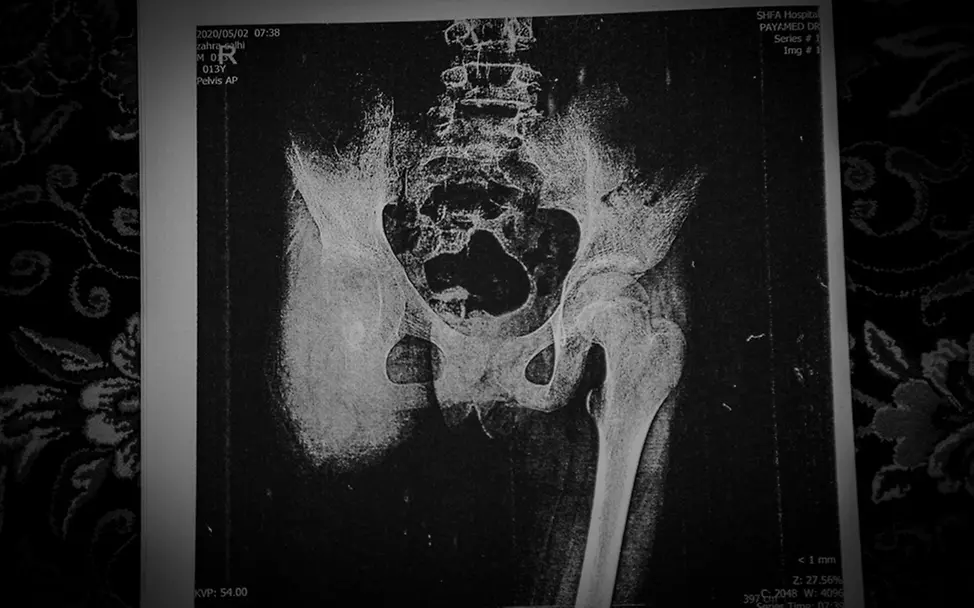

Zahra had a dream: to be as light as a butterfly. And to fly. One day. In this world, however, her dream will no longer come true. Zahra died at the age of 13. She spent the last three years of her life bravely fighting against bone cancer. One awful round after another. It began with chemotherapy, which was so futile that Zahra first had to have her right leg amputated, then required lumbar vertebrae surgery that resulted in her spinal cord being damaged and left her paraplegic.

Iranian photographer Shayan Hajinajaf accompanied the girl’s ordeal intensively and with great empathy: they shared moments when Zahra smiled and moments when she could barely breathe; moments of comfort with her family and moments alone in a hospital bed, attempts to walk at the beginning and the sheer agony at the end. According to the Iranian Pediatric Blood and Cancer Association, 2500 children under the age of 15 are diagnosed with cancer annually in Iran.